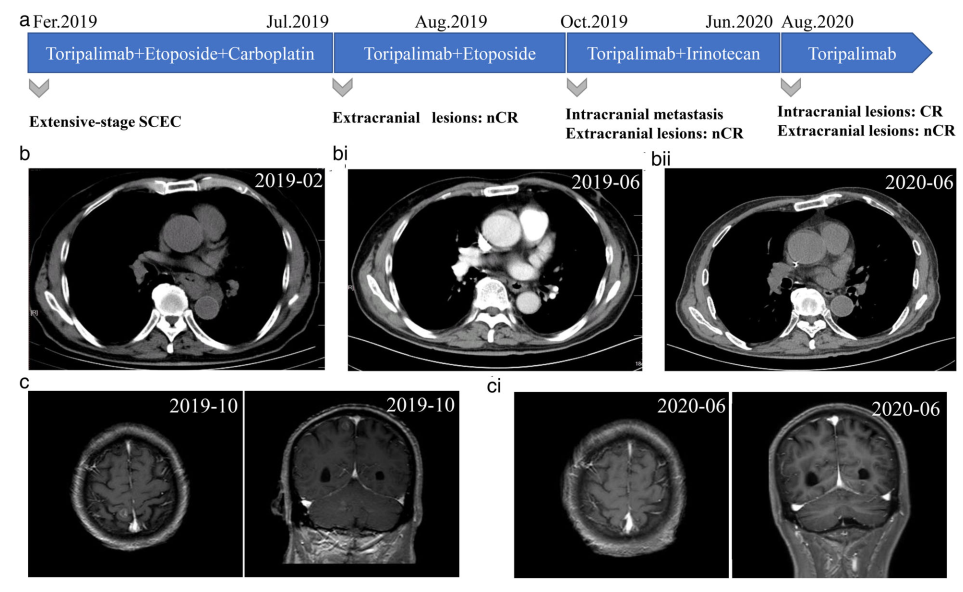

活检样本进行全外显子组测序和IHC分析。MDM2扩增,PD-L1阳性表达(1.83%),肿瘤突变负荷为2.99 Muts/Mb。自2019年2月至7月期间,行6周期特瑞普利单抗(PD-1单抗;D5,240mg)联合依托泊苷(D1~5,100mg)/卡铂(D1,450mg)治疗。

增强CT未见肝脏转移灶明显强化,纵隔4R区淋巴结及肺转移灶完全消失。钡餐造影显示食管壁光滑。复查胃镜示食管病变完全消除,呈瘢痕样改变。患者获得了接近完全缓解(nCR)(图2)。随后给予特瑞普利单抗(D4,240mg)联合依托泊苷(D1~4,100mg)维持治疗。不幸的是,于2019年10月发现颅内转移。因此,立即给予特瑞普利单抗(D2,240mg)加伊立替康(D1,300mg)4周期,并进行1疗程的脑转移放疗。2020年6月,颅内病变达到完全缓解(CR),颅外病变达到nCR。随后给予特瑞普利单抗(240mg)治疗。目前,该患者的总生存(OS)已经超过19个月(图3),目前情况稳定,没有任何严重的不良反应。

除手术和化疗外,小细胞食管癌患者缺少治疗选择,预后很差,既往研究显示,这类患者的中位OS仅为11.1个月。而该例患者使用免疫治疗联合化疗,显示出更有效且持久的获益(OS>19个月)。免疫治疗联合化疗对于小细胞食管癌可能是一种合理选择。此外,该发现需要良好设计的临床研究来进一步证实。

免疫检查点抑制剂(ICIs)是近十年来第一类为小细胞肺癌患者带来预后改善的药物。在IMpower 133 和CASPIAN研究中,小细胞肺癌患者的OS显著改善,且耐受性良好,ICIs成为小细胞肺癌患者的一线标准治疗。此外,在消化道肿瘤中,免疫治疗联合化疗也成为趋势,该病例虽然PD-L1表达低,但是OS仍超过19个月,超过小细胞食管癌研究中的中位生存(一项例1176例小细胞食管癌病例的研究显示中位OS为11.1个月)。尽管这个病例具有一定的偶然性,但仍提示免疫治疗联合化疗是小细胞食管癌的潜在治疗选择。